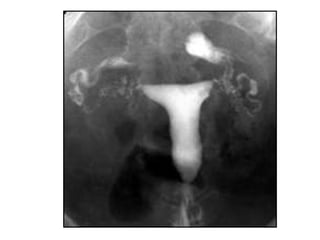

Histerosalpingografía

 Es la técnica clásica para el estudio

 Proporciona información acerca del canal

endometrial y cervical, así como de la

permeabilidad de las trompas

 Principales limitaciones: no permite valorar el

contorno uterino externo, e implica exposición

a radiación en pacientes jóvenes que están

siendo estudiadas por problemas de fertilidad